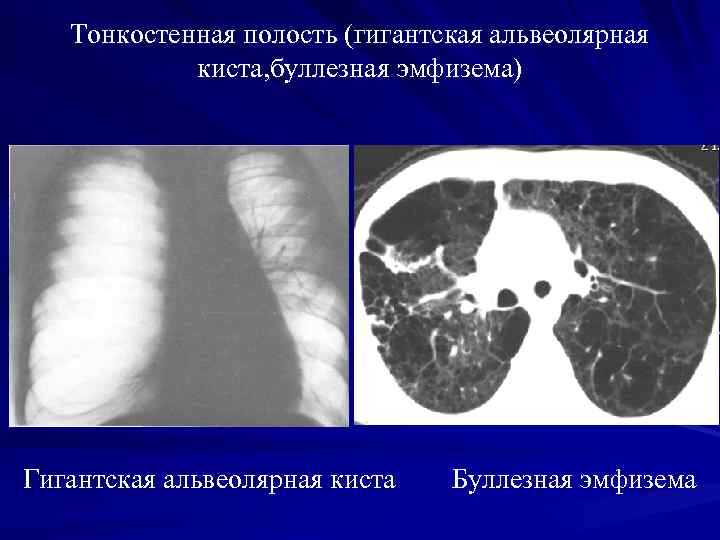

Буллёзная болезнь и пневмоторакс